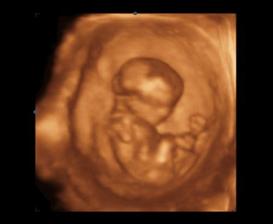

14.1.2010 3D ultrazvuk podľa PM presne 13tt+0 , na drobčeka sa bol pozrieť 1.krat aj tatinko, bolo to krásne 🙂 /////